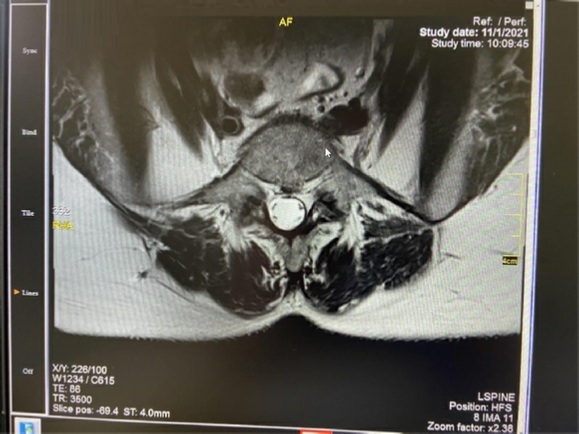

Στις δύο ανωτέρω εικόνες είναι εμφανής η έντονη εκφύλιση του μεσοσπονδυλίου δίσκου Ο5-

Αυτή η περίπτωση είναι ιδανική για διενέργεια πρόσθιας διασωματικής σπονδυλοδεσίας, η οποία και διενεργήθηκε με τη χρήση ευρέως κλωβού και μίξη αυτομοσχεύματος από το λαγόνιο (μέσω της ίδιας τομής) και DBM. Σταθεροποίηση με τρεις βίδες με πολύ καλή συγκράτηση και συμπίεση του κλωβού. Ακολουθούν οι μετεγχειρητικές ακτινογραφίες.